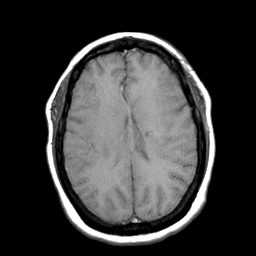

Cerebral hemorrhage, MR Study mr-t1 -- Slice #15

[Home][Help][Clinical] Slice 15